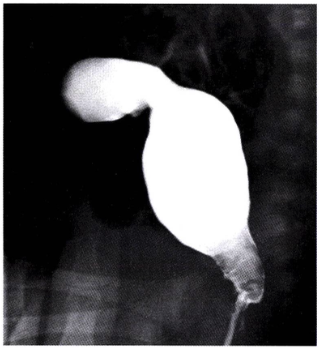

• 공기 또는 바륨 관장: 진단과 동시에 치료 목적으로 시행될 수 있음. 장이 말려 들어간 부위가 '나선형 용수철(coil spring)' 모양으로 보이면서 filling defect 확인